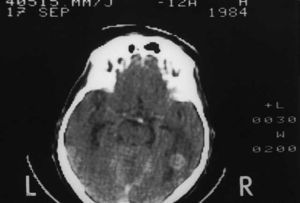

TC cerebral. La realizaremos después de haber descartado la presencia de causas metabólicas o farmacológicas. Suele ser la prueba diagnóstica en la mayoría de pacientes.

La decisión terapéutica requiere una valoración multidisciplinaria. En función de todos estos parámetros optaremos por el tratamiento quirúrgico (exéresis de la lesión/lesiones), la irradiación holocraneal, la radiocirugía (administración de altas dosis de radioterapia en un campo reducido), la quimioterapia, o tratamiento exclusivamente sintomático (situaciones muy avanzadas) (fig. 2).

Fig. 2. Metástasis cerebrales de origen pulmonar con edema cerebral secundario.